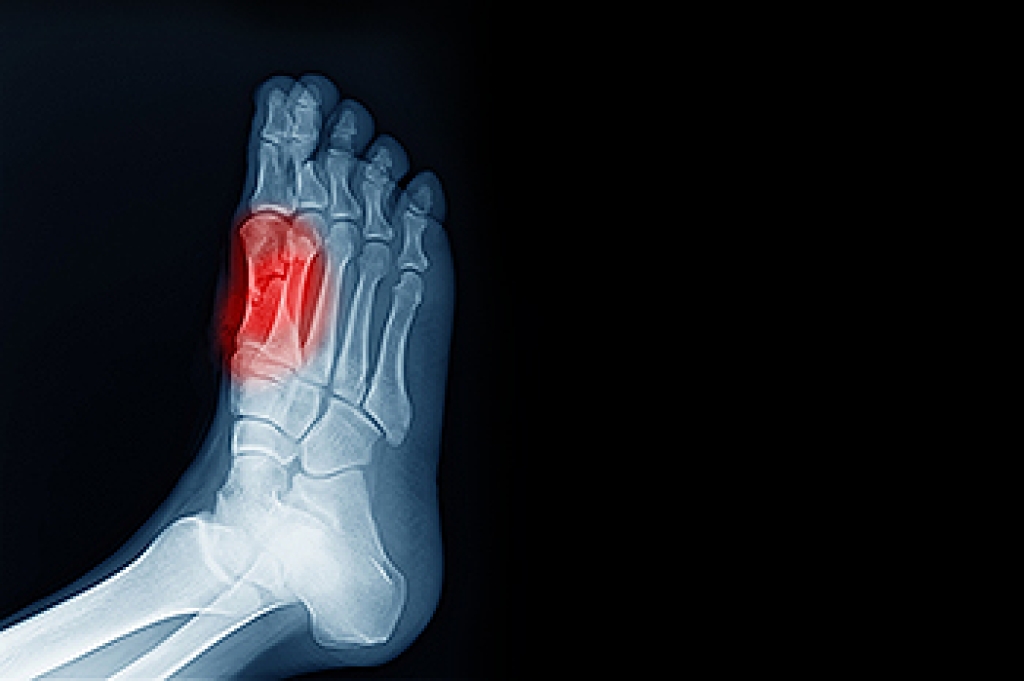

While it may not seem apparent with small ulcers on the foot, for diabetics, any size ulcer can become infected. Diabetics often also suffer from neuropathy, or nerve loss. This means they might not even feel when they have an ulcer on their foot. If the wound becomes severely infected, amputation may be necessary. Therefore, it is of the upmost importance to properly care for any and all foot wounds.

The best way to care for foot wounds is to prevent them. For diabetics, this means daily inspections of the feet for any signs of abnormalities or ulcers. It is also recommended to see a podiatrist several times a year for a foot inspection. If you do have an ulcer, run the wound under water to clear dirt from the wound; then apply antibiotic ointment to the wound and cover with a bandage. Bandages should be changed daily and keeping pressure off the wound is smart. It is advised to see a podiatrist, who can keep an eye on it.